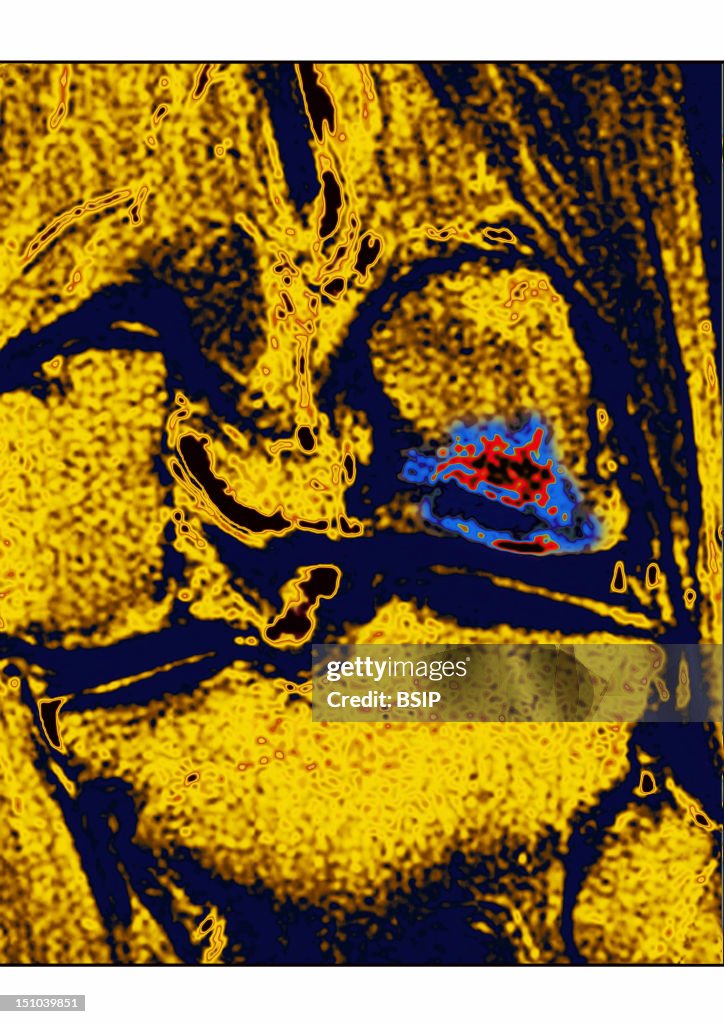

Exostosis, Mri

This Frontal Mri Image Of The Knee Shows A Exostosis Of The Thighbone. (Photo By BSIP/UIG Via Getty Images)